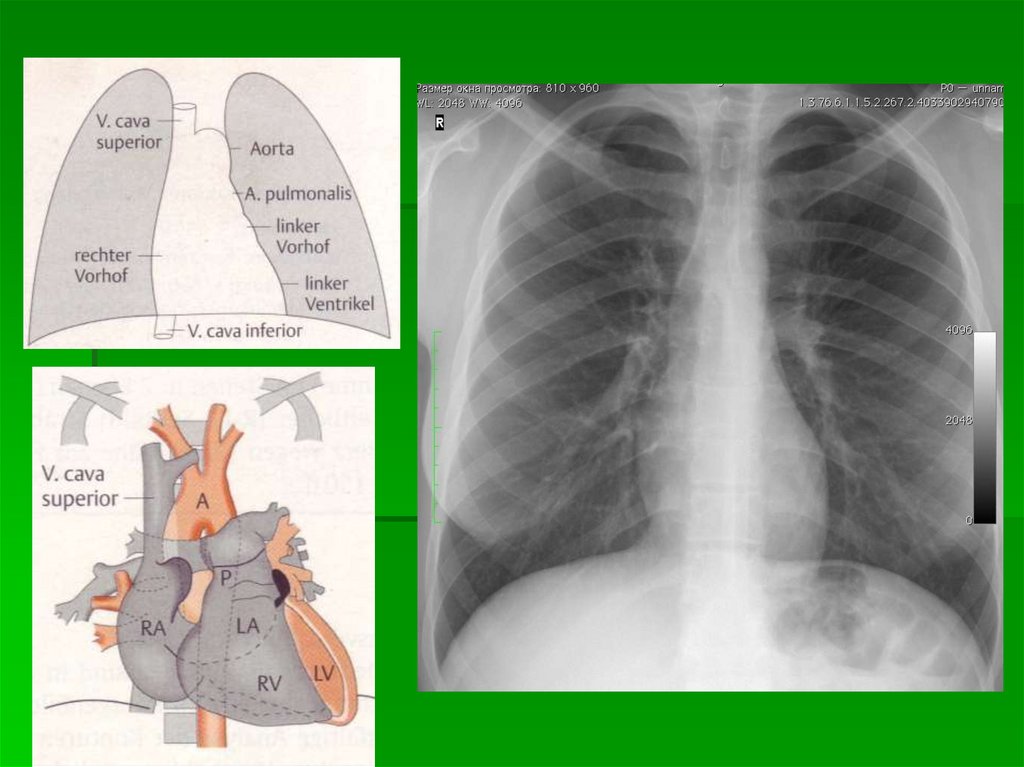

Схема расположения камер сердца и

крупных сосудов при контрастном

исследовании

1 — трахея, 2 — правый главный бронх, 3

— правый верхнедолевой бронх, 4 —

верхняя полая вена, 5 — ортопроекция

артерии правого III сегмента, 6 — правая

верхнедолевая вена, 7 — нисходящая

ветвь правой легочной артерии, 8 —

правая базальная вена (из нижней

группы легочных вен), 9 — контур

диафрагмы справа, 10 — дуга аорты, 11

— ортоградная проекция левой легочной

артерии, 12 — артерия III левого

легочного сегмента, 13 — левая

верхнедолевая вена, 14 — левая

нижнедолевая вена, 15 — легочный

ствол, 16 — левое предсердие, 17 —

левый желудочек, 18 — левый

верхнедолевой бронх, 19 — правая

легочная артерия, 20 — левый главный

бронх.